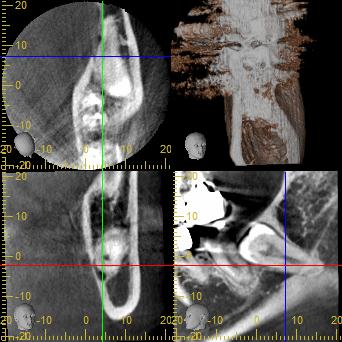

今回は口腔外科の分野から親知らずのCT検査、特に神経との関係についてです.

従来のレントゲン撮影は立体の構造を2次元に押し付けたようなもので、

症例です

根の先端部分で神経と接しており、

方向によっては舌側の骨を破る恐れもあるケースです。

神経と近接しているのはわかりますが、麻痺が出るかどうかは抜歯してみないとわかりません。リスクが高いと言えますが、必ず神経麻痺が出るわけではありません。